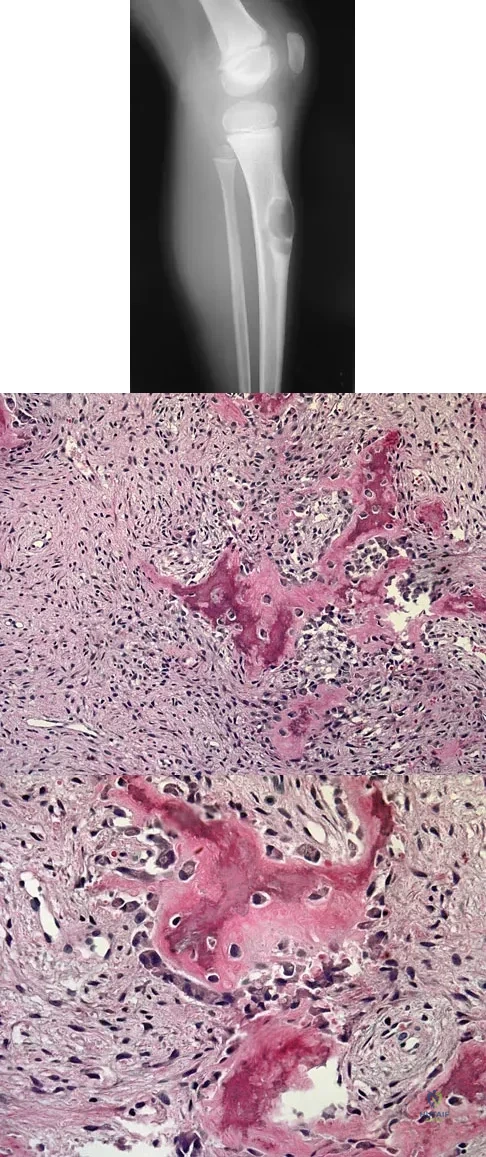

A 16-year-old boy has had thigh pain for the past several months. He denies any history of trauma. Examination reveals a large, deeply fixed, soft-tissue mass in the thigh. Laboratory results show an elevated erythrocyte sedimentation rate (ESR) and leukocytosis. A plain radiograph and MRI scan are shown in Figures 1a and 1b. Biopsy specimens are shown in Figures 1c and 1d. What is the most likely diagnosis?

Explanation